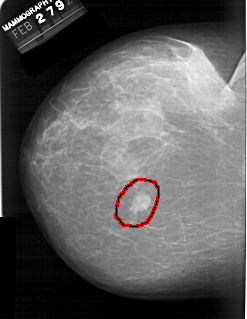

A_1389_1.LEFT_CC

LEFT_CC LINES 6046 PIXELS_PER_LINE 4681 BITS_PER_PIXEL 12 RESOLUTION 43.5 OVERLAY

FILE: A_1389_1.LEFT_CC.OVERLAY

TOTAL_ABNORMALITIES 1

ABNORMALITY 1

LESION_TYPE MASS SHAPE LOBULATED MARGINS CIRCUMSCRIBED

ASSESSMENT 4

SUBTLETY 5

PATHOLOGY BENIGN

TOTAL_OUTLINES 1

BOUNDARY